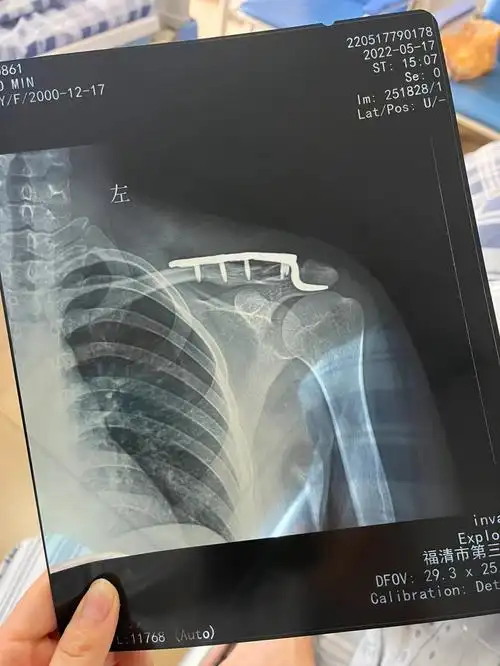

左锁骨肩峰端骨折